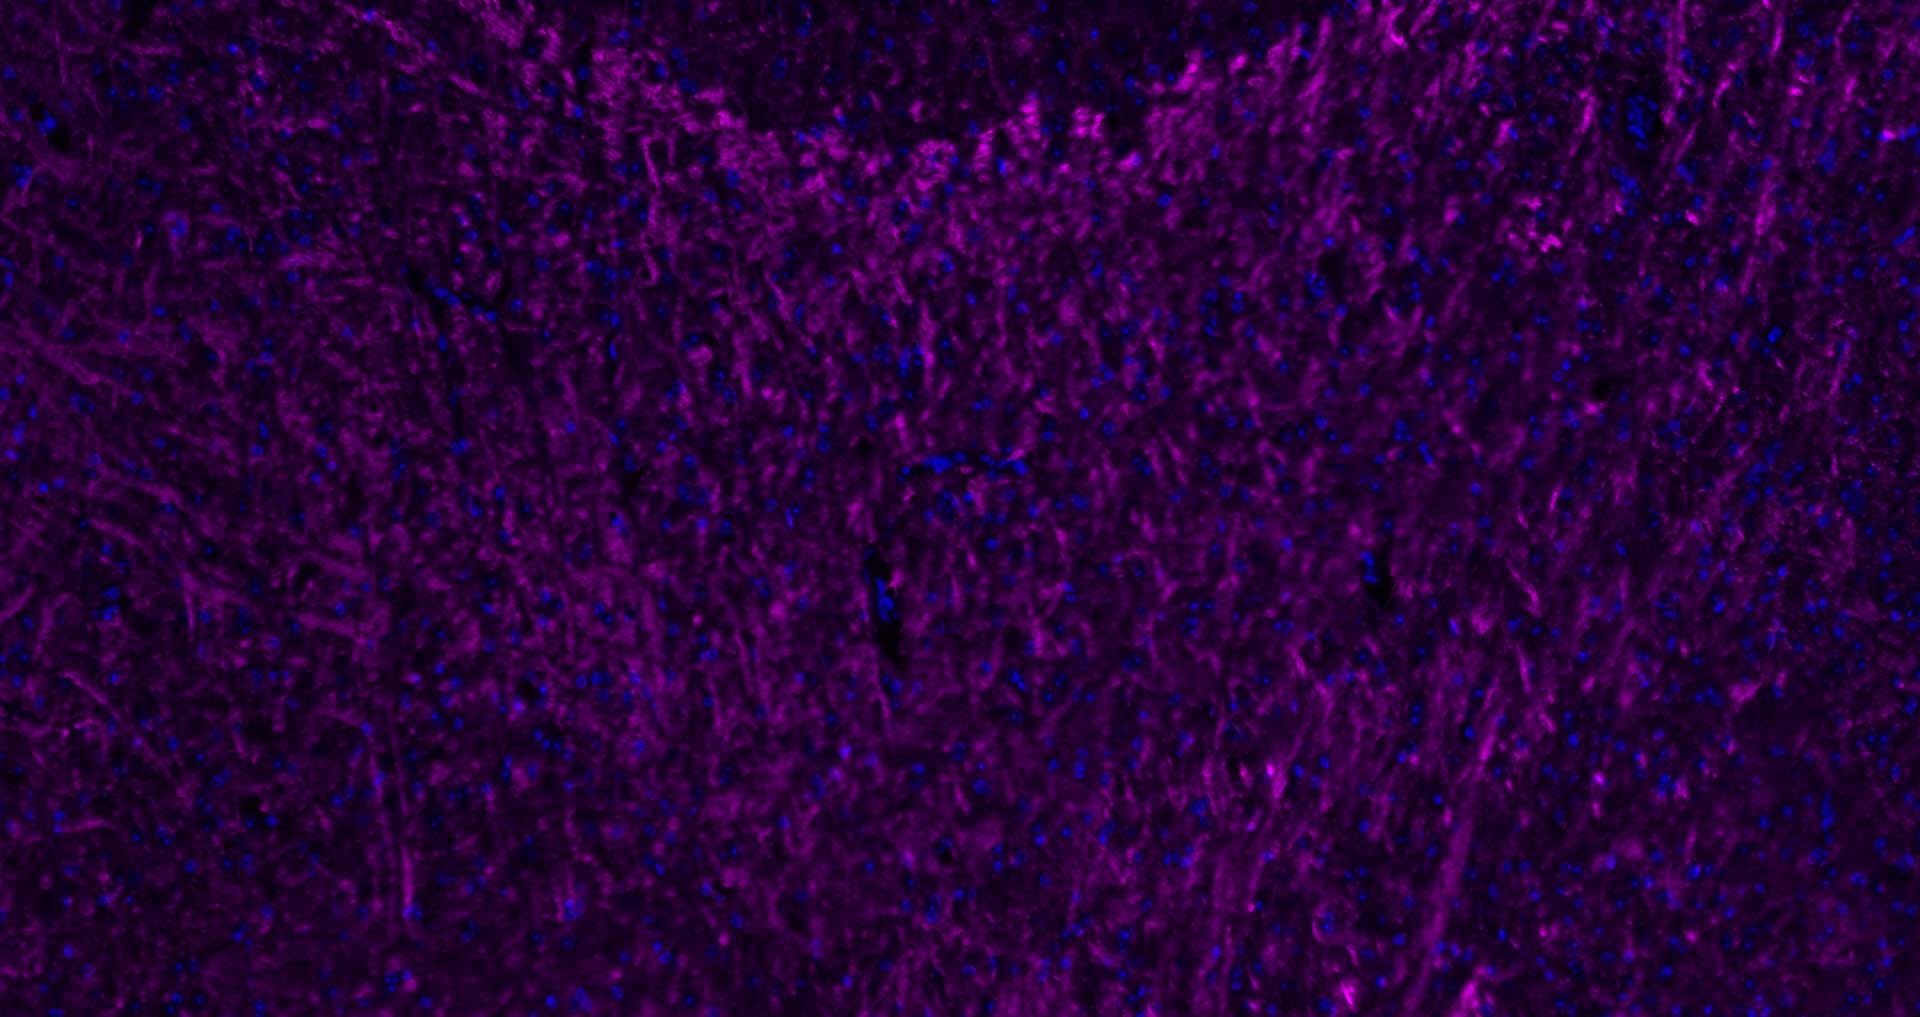

| 背景资料 | Oligodendrocyte Marker The classic group of Myelin basic protein (MBP) isoforms (isoforms 4 to 14) are with PLP the most abundant protein components of the myelin membrane in the CNS. They have a role in both its formation and stabilization. The smaller isoforms might have an important role in remyelination of denuded axons in multiple sclerosis. The non classic group of MBP isoforms (isoforms 1 to 3/Golli MBPs) may preferentially have a role in the early developing brain long before myelination, maybe as components of transcriptional complexes, and may also be involved in signaling pathways in T cells and neural cells. Differential splicing events combined to optional posttranslational modifications give a wide spectrum of isomers, each of them having maybe a specialized function. |

| {IHC-P} | {1:500-2000} |

| {IHC-F} | {1:500-2000} |

文献和实验[IF={{ 8.352 }}] {Chanjuan Dong. et al. Graphene-based conductive fibrous scaffold boosts sciatic nerve regeneration and functional recovery upon electrical stimulation. Appl Mater Today. 2020 Dec;21:100870} {IHC} {Rat}